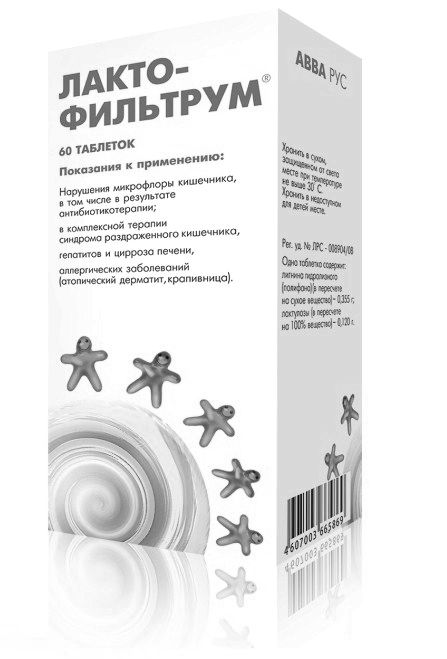

- Випускається в 2 варіантах: по 30 і по 60 таблеток.

- Ціна - від 250 до 400 рублів. Залежить від кількості таблеток в блістері і прейскуранта конкретної аптеки.

- Ліки проводиться в Укаїни.